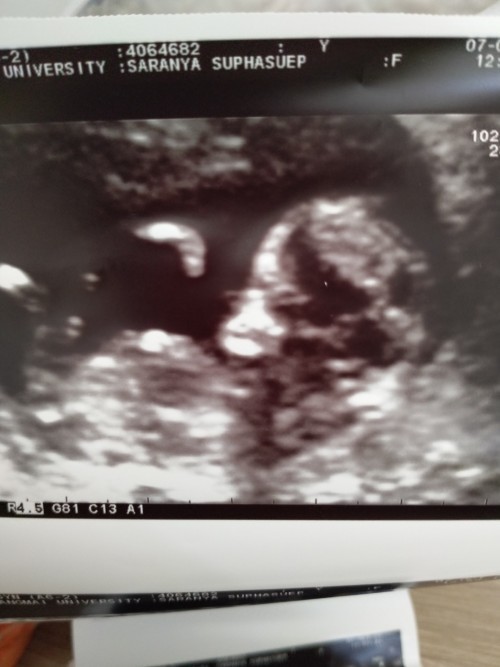

ตอนนั้น12weekรอลุ้นเพศวันที่9 วันที่9เข้าweekที่20คะ